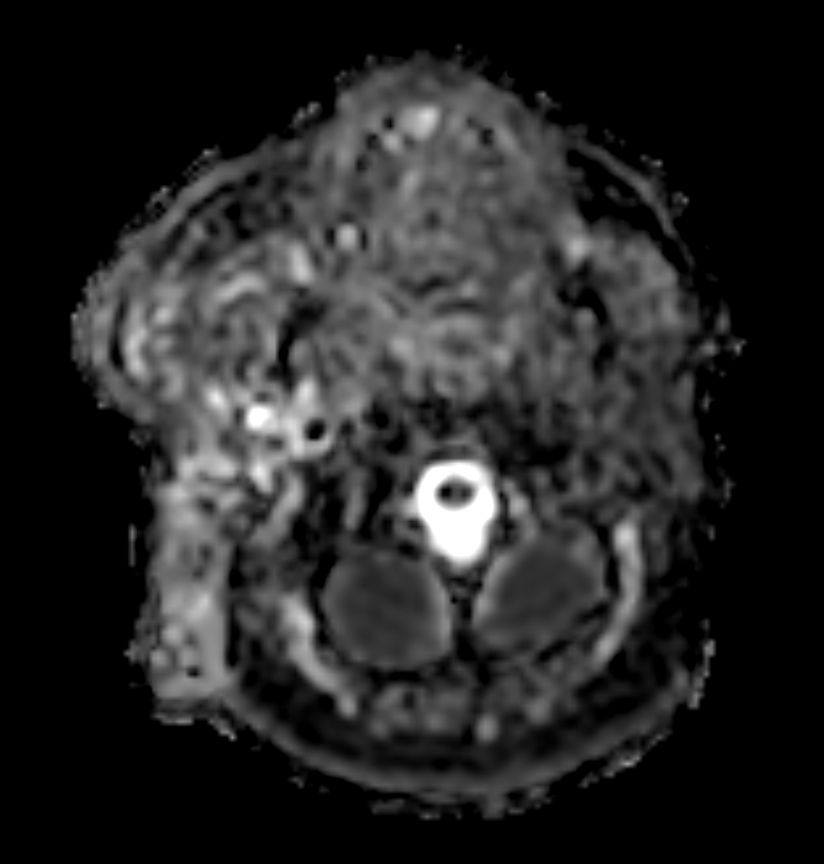

DWI TSE XD (b600)

DWI TSE XD (ADC)